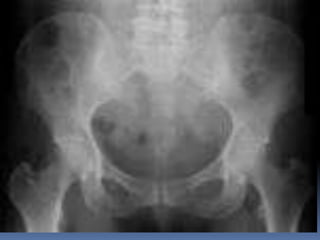

CRITERIOS DE EVALUACION P.S.A.  Apreciar desde el abdomen superior hasta la sínfisis del pubis.  Lumbares, pelvis y ultimas costillas sin rotación.  Apófisis espinosas en el centro de cuerpos vertebrales.  Ver el bazo, riñones, psoas y “borde inferior hepático

INTERPRETACION  Estructuras óseas (densidades).  Tejido blando  Psoas.  Bazo  Niveles Hidroareos.  I.D.  Colon  Silueta Renal